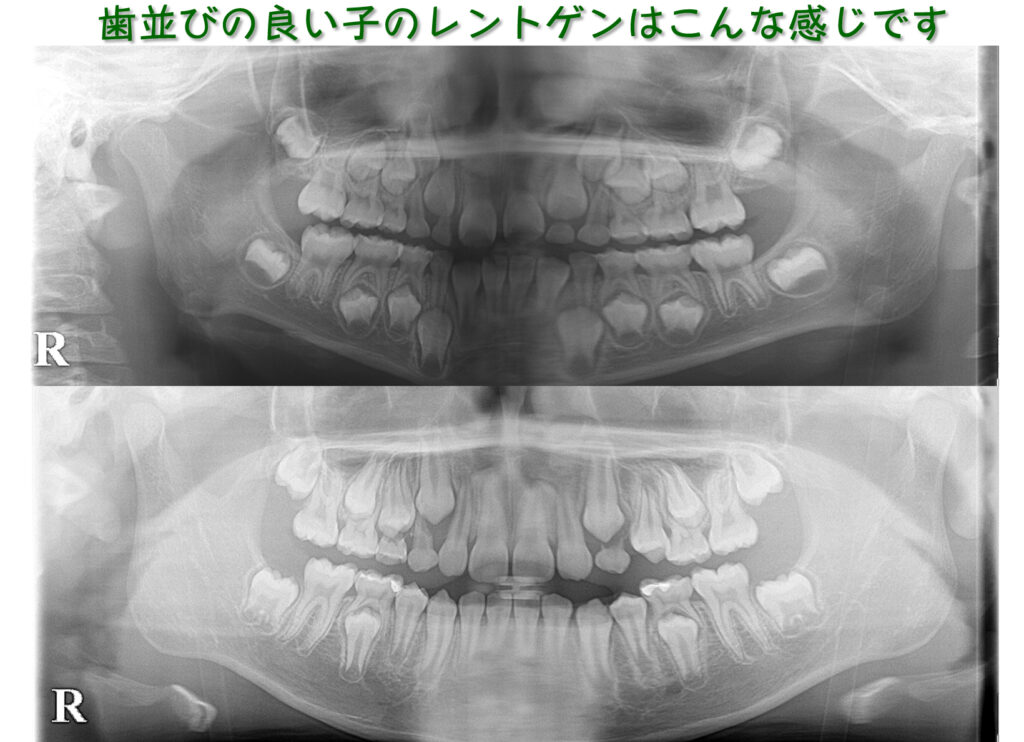

レントゲンを見ると永久歯と永久歯が接近しています。

レントゲンでは、上の犬歯の生えるスペースがないように見えます。この段階で「矯正が必要です」と言われることもあるかもしれませんが…

私達は何もせず経過観察することにしました。

何もしていないのに上の犬歯のためのスペースができてきました。

順調に乳歯から永久歯への交換が進んでいます。

さらに経過を観察しています。

美しい歯列が完成しました。口腔機能訓練も一切行っていません。

前歯にスキマがある方が、あとできれいに並ぶ場合も多いのです。